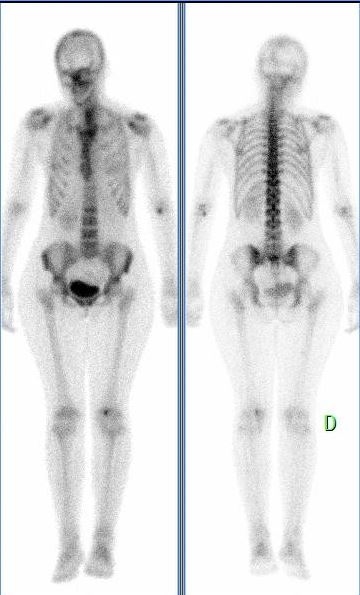

Patiente de 38 ans, découverte fortuite d’une lésion hyperfixante métaphysaire inférieure gauche.

Examen réalisé dans le cadre d’une doleur du genou droit.

Lésion métaphysaire fémorale inférieure, taille inférieure à 6 cm

Respect de la corticale (pas d’encoche endostée)

Matrice cartilagineuse présente

Fixation inferieure à la fixation de l’EIAS

Pas de critère d’agressivité: lésion évoquant un enchondrome.

Enchondrome fémoral inférieur gauche de découverte fortuite.

Pas de signe d’agressivité, proposition d’une surveillance à 6 mois puis 1 an.